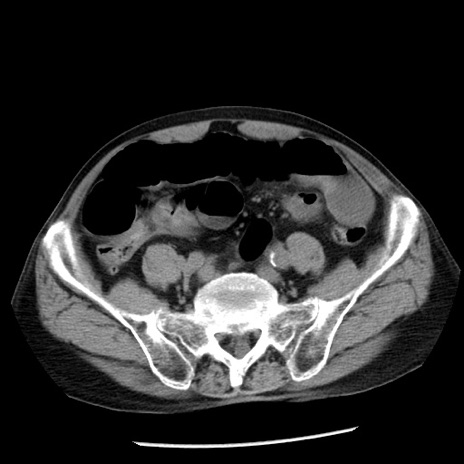

症例26(横断像)

【症例】80歳代男性

【主訴】嘔吐

【現病歴】昨晩2回嘔吐あり、今朝になっても嘔吐あり。来院。

【既往歴】胃潰瘍

【身体所見】意識清明、BT 37.6℃、BP 166/95mmHg、HR 100bpm、SpO2 97%、腹部:平坦・軟、腸蠕動音聴取良好、圧痛なし。

【データ】WBC 21900、CRP 1.46